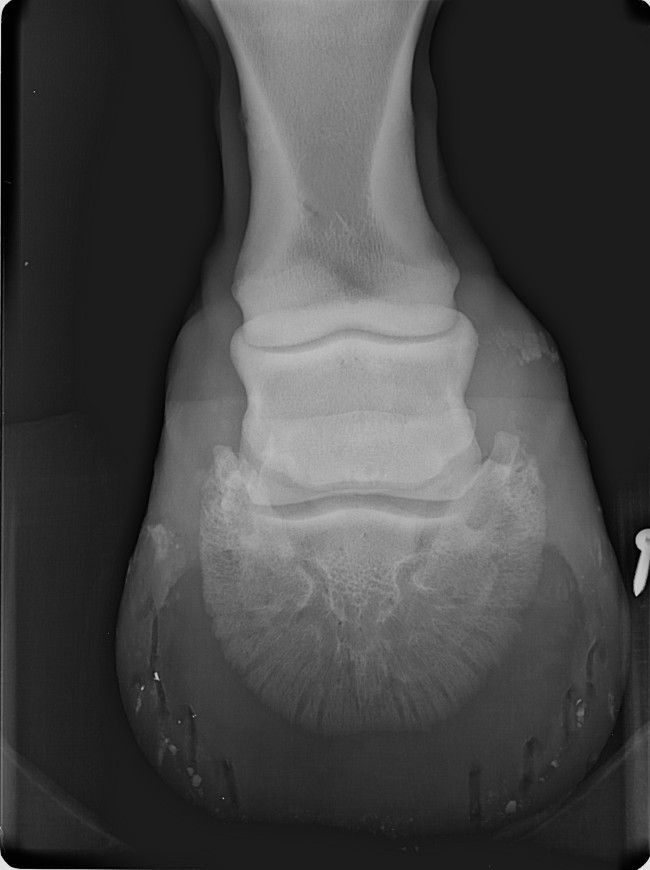

| Dire merci | les premières radios sont de juillet 2012 Voici les radios de l'antérieur droit fin septembre 2012 ![]() et celles de l'antérieur gauche ![]() ![]() |

Déconnecté | ben oui en voyant les radios, je me suis dit ostéïte direct. d'ailleurs elles sont assez impressionnantes. l'ostéïte a un caractère assez definitif,l'os ne peux pas se reminéraliser. les anti inflammatoires, c'est pour eviter qu'il y a ai une nouvelle infection qui déminéralise encore plus. quant à le remonter ....vu tes radios ... il faut imaginer que ses phalanges sont devenues aussi légère que de la roche volcanique pleine de trous ... au moindre choc, il va souffrir, et il risque des fissures de fatigue et de traumatisme aussi ... franchement, tes radios sont pas très encourageantes :S |